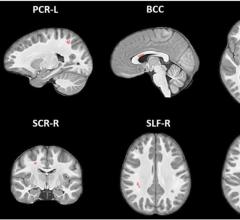

March 25, 2021 — A large study of brain magnetic resonance imaging (MRI) scans from 11,679 nine- and ten-year-old ...

February 17, 2021 — Diffusion weighted imaging and machine learning can successfully classify the diagnosis and ...